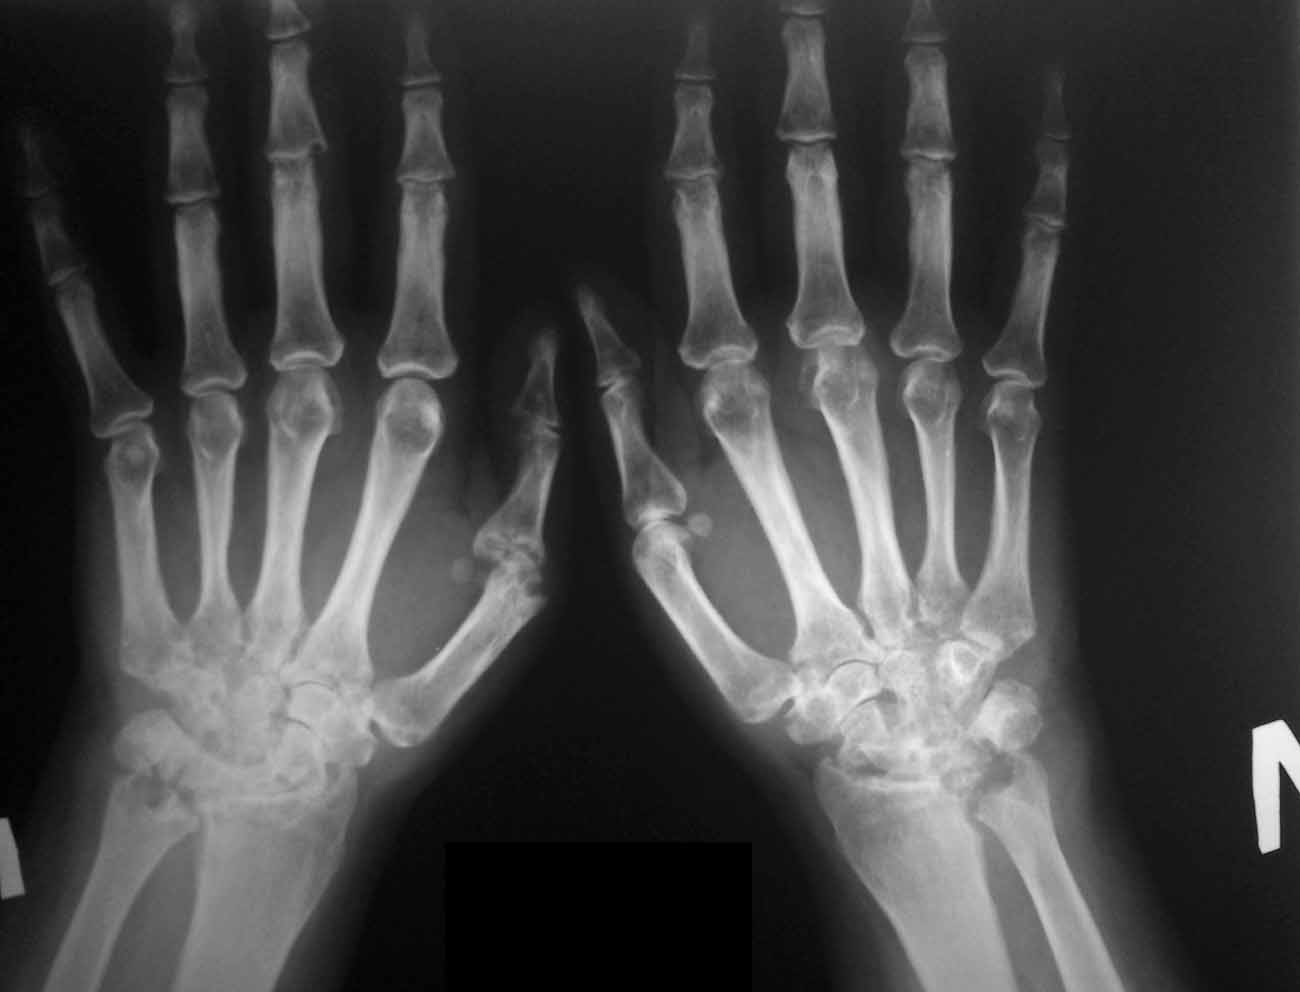

Симметричность по рядам, отсутствие сужения суставных щелей дистальных межфаланговых суставов и сужение суставных щелей проксимальных межфаланговых суставов, ульнарная деформация вторых пальцев, околосуставной остеопороз, кистовидные просветления и узуры в лучезапястных суставах – это классика ревматоидного артрита. Но изменения в костях запястий – это уже ретроклассика.